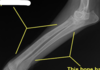

Cervical vertebral myelopathy "Wobbler syndrome"

Cervical vertebral malformation-malarticulation in a horse. Flexion of the cervical vertebrae results in stenosis of the spinal canal (asterisk). Flaring of caudal epiphysis (arrowhead), can also contribute to spinal compression

Cervical vertebral malformation-matriculation in a horse, Osteochondrosis of the articular facet joints can contribute to the intervertebral joint instability